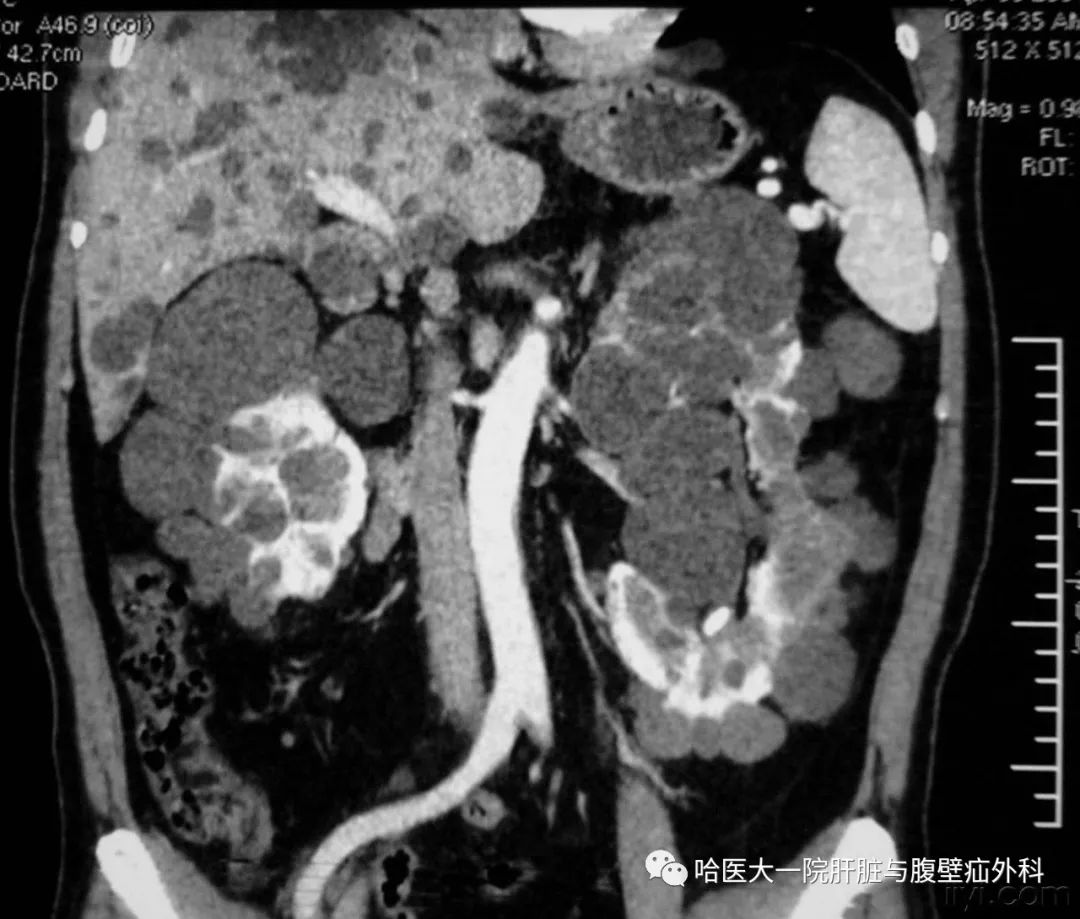

典型多囊肝

多囊肝,是一种常染色体显性遗传病,表现为肝脏的多发性弥漫损害,囊肿间的肝细胞正常,多合并多囊肾,同时在胰腺、脾脏、双肺及女性卵巢可发现囊性病变。多囊肝合并多囊肾致病基因位于人第16对常染色体上,DNA分析可作为疾病无症状时和产前的早期诊断。

(1)B超检查:是诊断多囊肝可靠而简易的方法。边界清楚的多发性无回声区是本病典型表现。可见肝大,肝内无回声病灶众多,相互连成片,由纤细光滑的囊壁分隔成大小不等的多房囊腔。

(2)CT检查:可明确囊肿的大小、数目、解剖位置,并可发现1~2cm肝囊肿。CT平扫表现为肝内弥漫大小不一的水样低密度影,边缘光滑清楚,CT增强后无强化。

图片